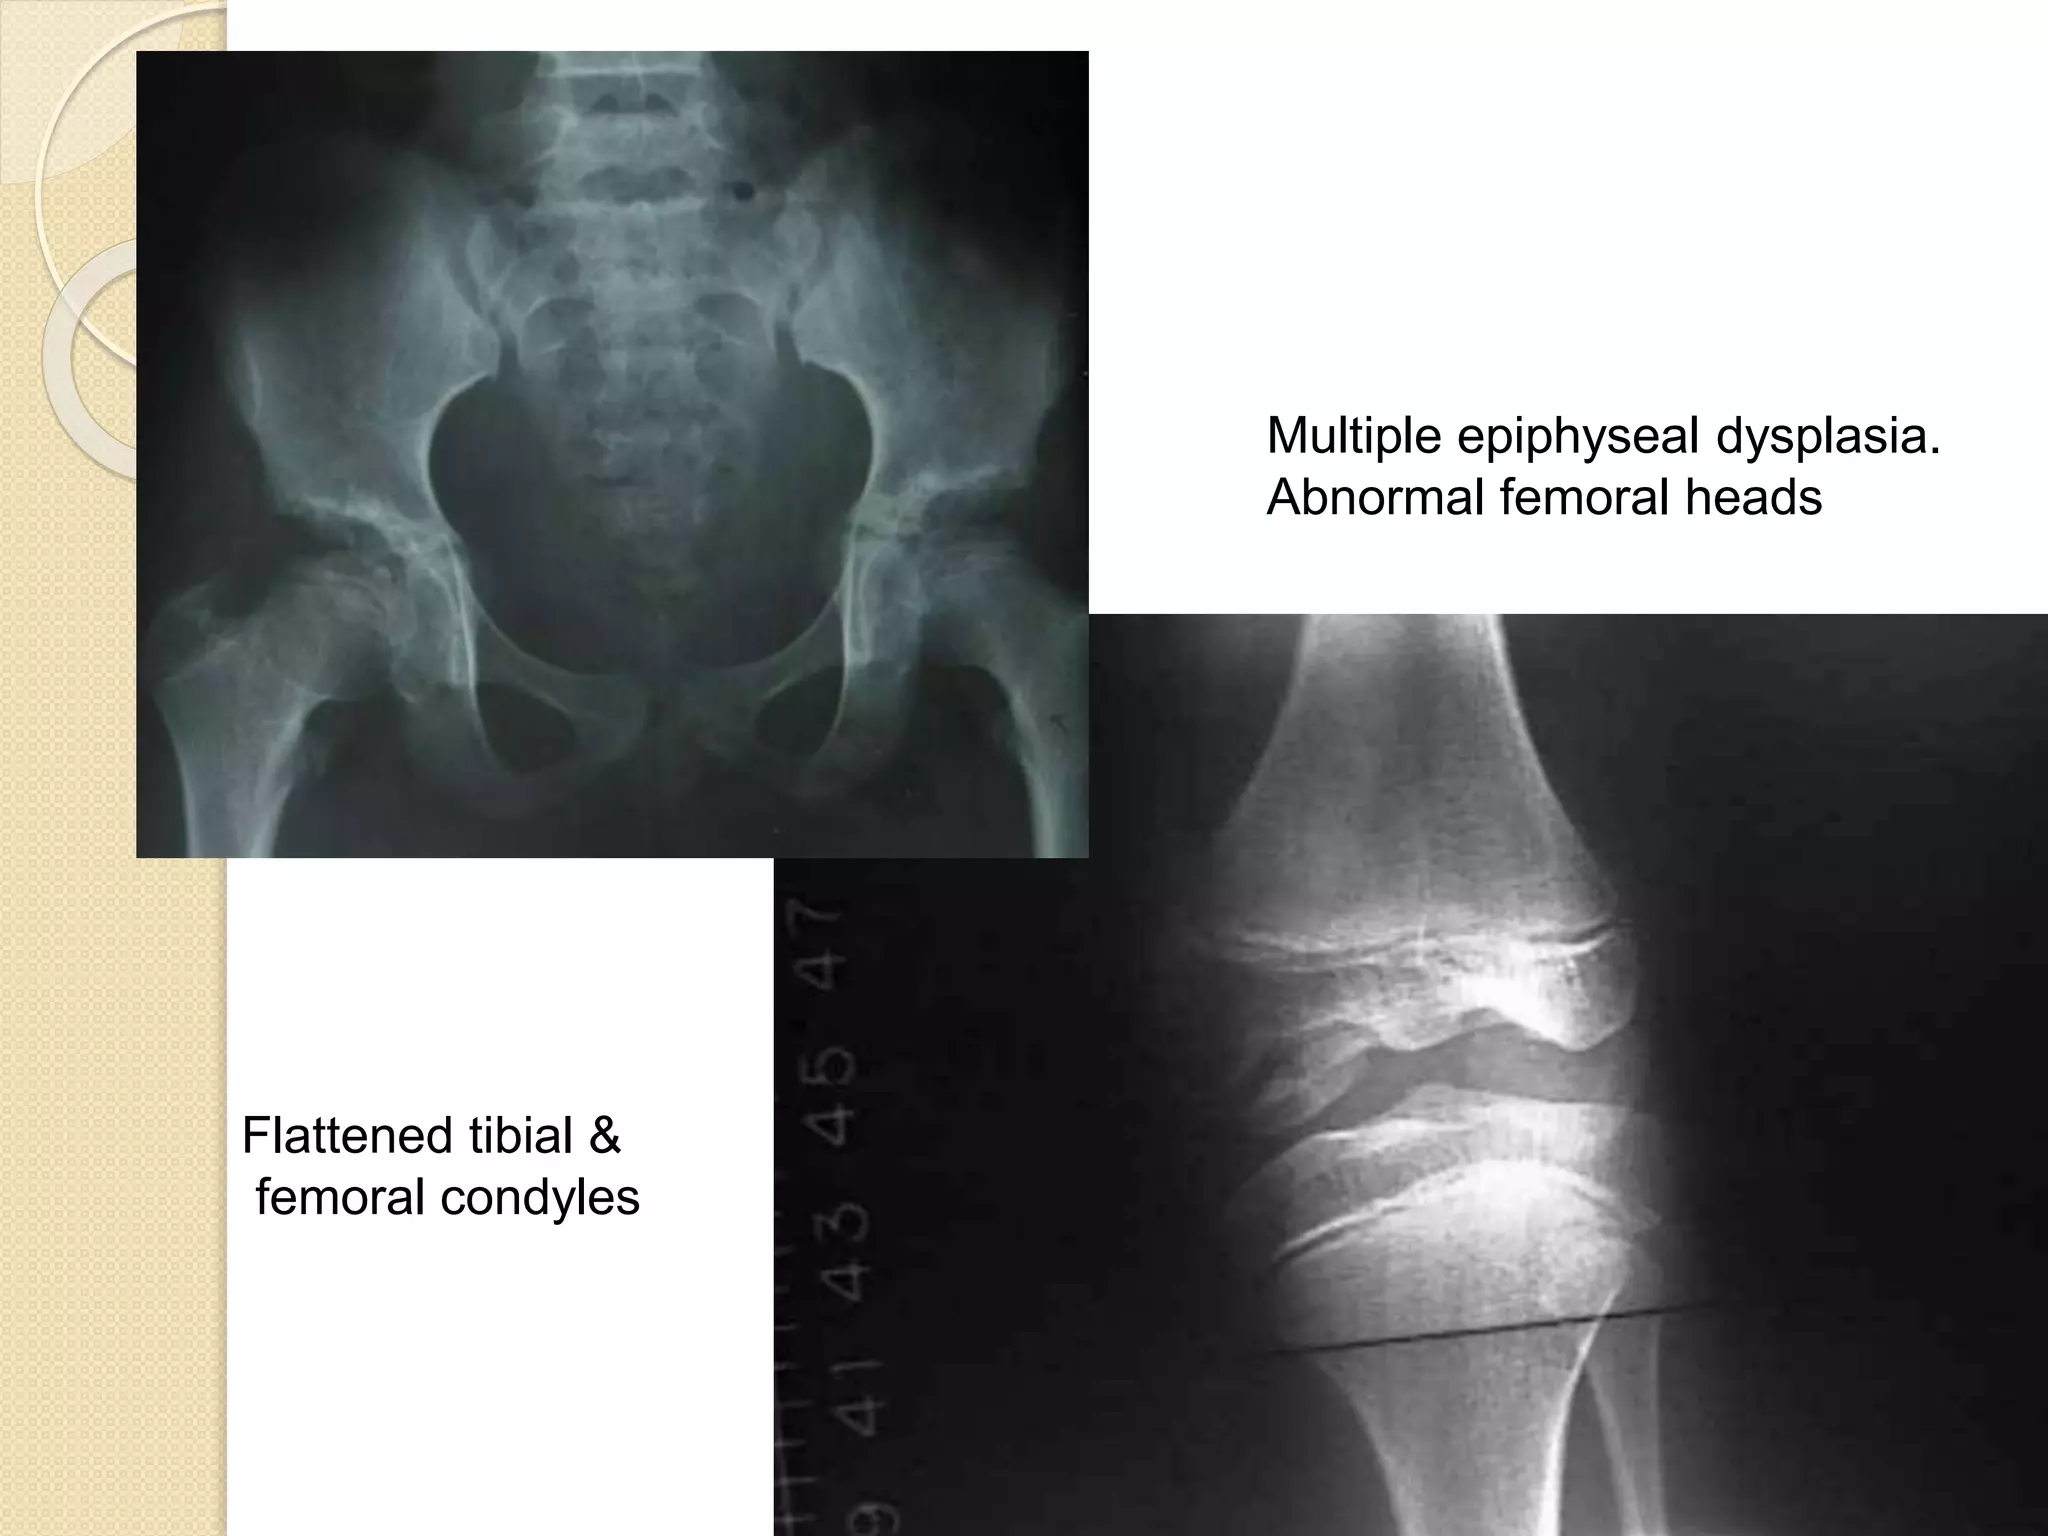

MULTIPLE EPIPHYSEAL

DYSPLASIA

 COMP gene mutation(Cartilage

oligomeric matrix protein )

 Prevalence of MED was 9 per 100,000

 Short-limbed, disproportionate

dwarfism often not manifested until

between the ages of 5 and 14.

 A mild form (Ribbing) and a more

severe form (Fairbanks) exist

 Waddling gait, and early hip arthritis

are common

 Irregular, delayed ossification at

multiple epiphyses

 Short, stunted metacarpals and

metatarsals, irregular proximal femora,

abnormal ossification (flattened tibial &

femoral condyles, patella

with double layer),

valgus knees

Multiple epiphyseal dysplasia.

Abnormal femoral heads

Flattened tibial &

femoral condyles